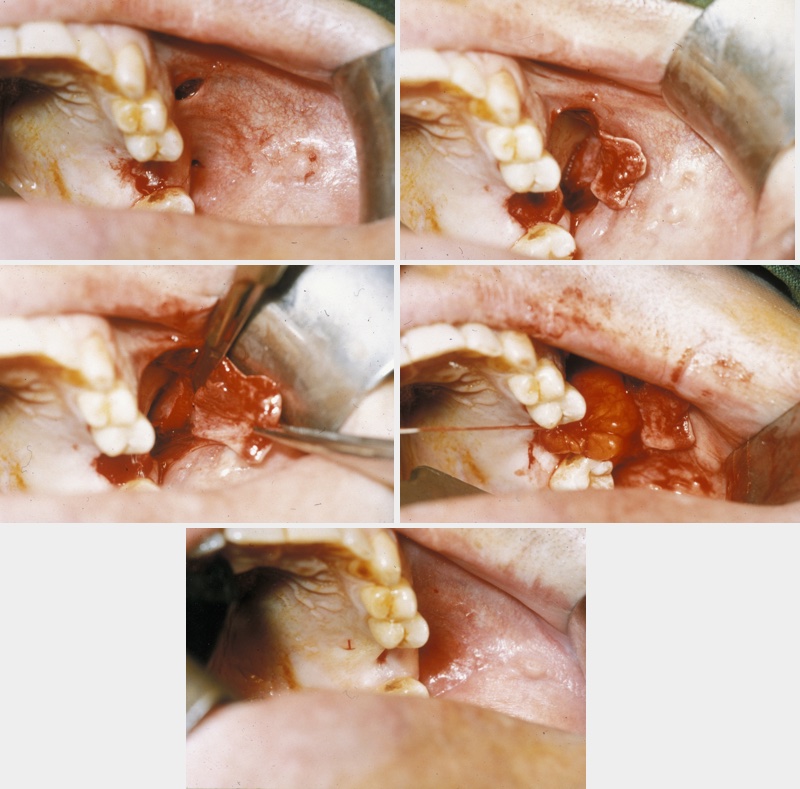

This procedure is approached using a similar incision to the buccal advancement flap (see above), but when the periosteum is incised, an artery clip is passed into the submucosa to identify the buccal fat pad (Figure 3).

Figure 3: The buccal pad of fat, a vascularised mobilizable entity which can be repositioned as a flap.

This is an axial flap that lends itself beautifully to the closure of oroantral fistulae. It can be used as an isolated flap where the vascularised fat fills the defect and is held in place with vertical mattress sutures (common, interrupted suture technique designed for minimal tension and scarring), thus allowing the raised buccal flap to be repositioned in the buccal sulcus to maintain depth (Figure 4).

Figure 4: Top left: Technique for buccal fat pad flaps – relieving incisions; top right: subperiosteal flap elevated; middle left: buccal fat pad exposed by periosteal incision; middle right: fat pad delivered and used as sole reconstruction to maintain sulcus depth; bottom: postoperative healing showing preserved cheeks and sulcus.